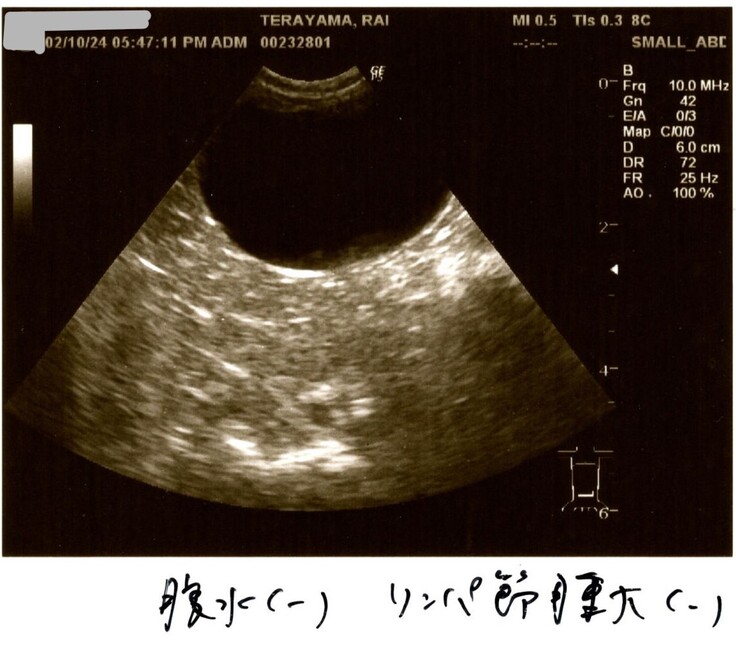

2/10検査結果

2/10はらいくんの2度目の検査結果を聞きました。

何と検査結果は全て改善していました!